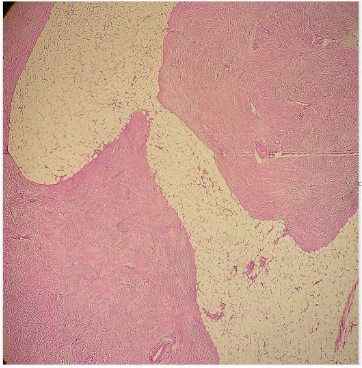

The operative material was analyzed at Institute of pathology, Faculty of Medicine in Skopje. The spleen was 277 g in weight and measured 10,5 x 9 x 4,5 cm. Gross examination of the cut sections at the splenic hilum showed solid white tissue with infiltrative borders measuring 4 x 3 x 2,5 cm. Near this tumor mass there was aneurismal dilatation of splenic artery with intraluminal clot and wall perforation (Figure 1a). Tissue specimens were fixed in formalin, embedded in paraffin and stained with hematoxylin & eosin.

Figure 1a: Gross cut sections of the spleen.